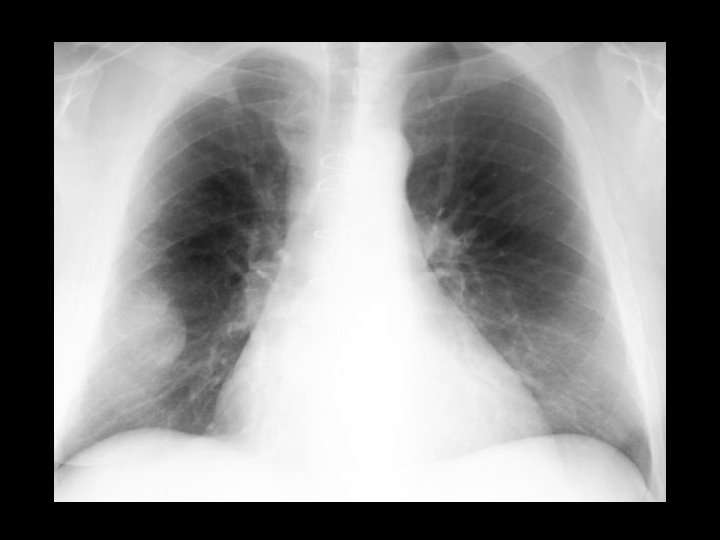

Knee fracture • Findings: – Lipohemarthrosis – No visible fracture but one is definitely present • ddx: – NONE! – This is an Aunt Minnie!